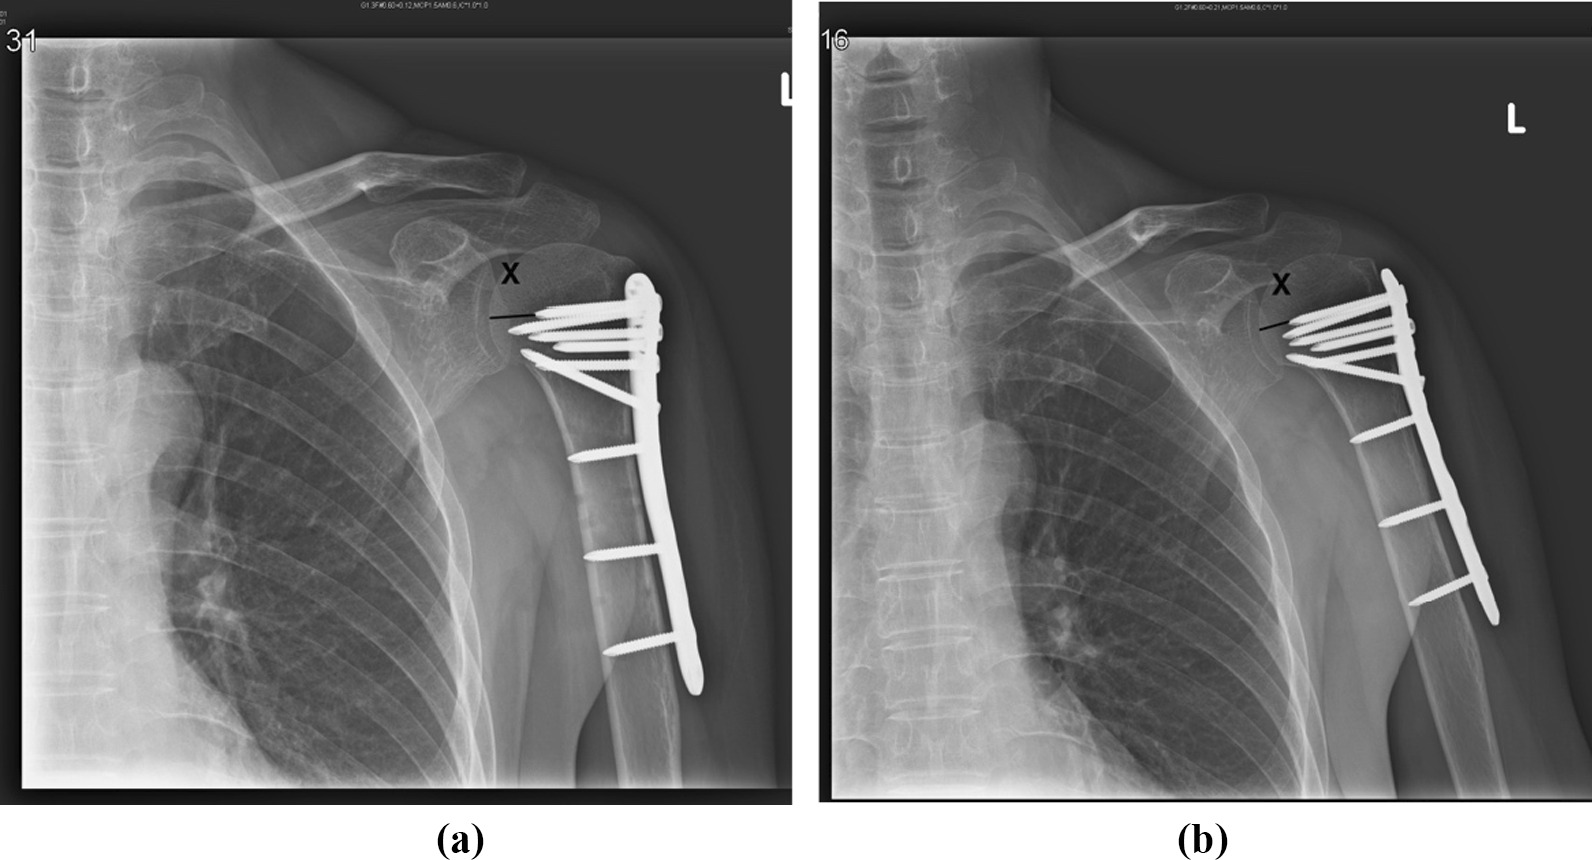

We used a modified method proposed by Carbone et al. [19] to assess the amount of humeral head impaction (Fig. 1). The measurement of X (the distance) using Carbone’s method yields the true distance between the tip of the most cranial screws and the humeral articular surface of the head. The differences between X in the baseline postoperative plain films and at the 12-month follow-up were used to determine the extent of impaction. A functional outcome was evaluated on the basis of the Constant function score at the 12-month follow-up.

Fig. 1.

a The distance between the most cranial screw and humeral articular distance is measured in external rotation A-P view 1 day postoperatively (X = 13.51 mm). b 12 months postoperatively, the distance between the screw tip and articular surface is measured in the same method (X = 10.09 mm). The amount of head impaction is 13.51 mm–10.09 mm = 3.42 mm in this patient